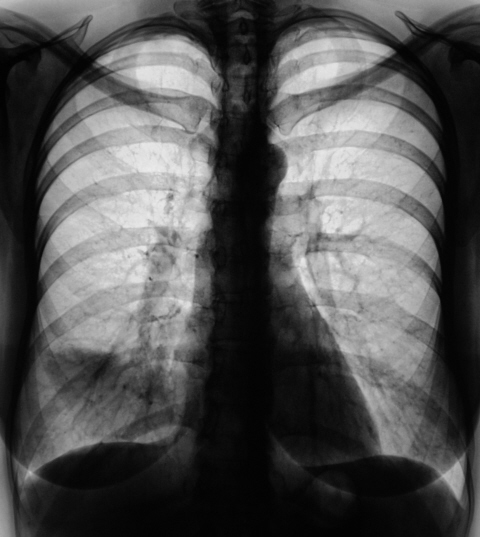

Снижение прозрачности верхней доли правого лёгкого с уменьшением объёма. "Культя" верхнедолевого бронха.

Снижение прозрачности переднего сегмента верхней доли правого лёгкого с уменьшением его объёма. Увеличение, расширение и гомогенизация тени правого корня.

Снижение прозрачности переднего сегмента верхней доли правого лёгкого (по всей видимости, за счет гиповентиляции) с объёмным уменьшением.

"Круглая тень" на уровне 2 ребра справа.